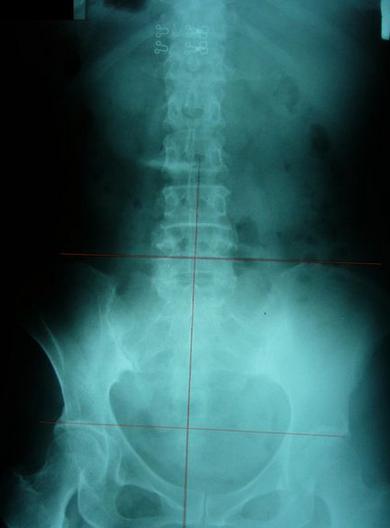

一般最常见到骨盆歪斜的案例包括产后骨盆不正、车祸、撞击、跌倒、姿势不良…等等造成。骨盆歪斜的典型症状包括腰部、髋臀部、腿、膝部疼痛。列举三个自在美国取得脊医执照以来曾经处理过骨盆歪斜相当明显的案例。都是骨盆部位曾经遭受撞击。案例A是超过十年以上的陈年车祸旧伤、另一案例B是急性摔伤(两天内)的案例。两者的X光片都依照美国脊医X摄影方式采站姿摄影评价。借此同时评价骨盆在重力(gravity)影响下的反应。也可以泯除躺歪斜摄影而造成图像不正的情况。最简单的评价要点包括骨盆高低边?中线是否穿越耻骨联合?左右两边是否对称?我简单的几条线一画,相信连外行人也可以看出明显的骨盆歪斜的情况。案例A属陈旧性伤害在调理约两个月后明显降低腰臀腿部的不舒服。而案例B属急性伤害,案例B在调理近三周后骨盆疼痛由原先的持续疼痛降低为完全不痛。之后的骨盆X光摄影重头评价也显示骨盆旋转的问题大幅改善。

案例A:右骨盆明显较低中线未穿过耻骨联合

理想骨盆相对位置:两边骨盆、股骨头对称等高、中线穿过腰椎荐椎与耻骨联合、骨盆环显现对称心形

严重不对称案例,伴随腰椎向左倾斜